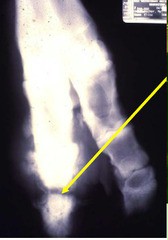

Septic Arthritis Radiograph.jpg